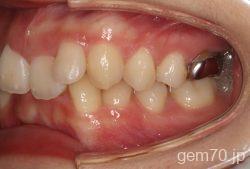

主訴)前歯のかみ合わせが深い

診断)過蓋咬合

年齢)21歳

使用装置)マルチブラケット装置(セラミックブラケット)

治療方法)4|4/4|4

治療期間) 2年8ヵ月 通院回数 32回